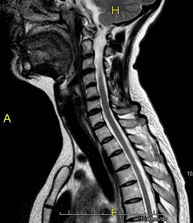

- RM Columna cervical

Prueba diagnóstica no invasiva que consiste en la obtención de imágenes de alta definición anatómica de la columna cervical mediante el empleo de un campo electromagnético y ondas de radio (con un emisor y un receptor). No utiliza radiación ionizante. Indicaciones: traumatismo, degeneración de la columna, hernias. - RM Columna dorsal